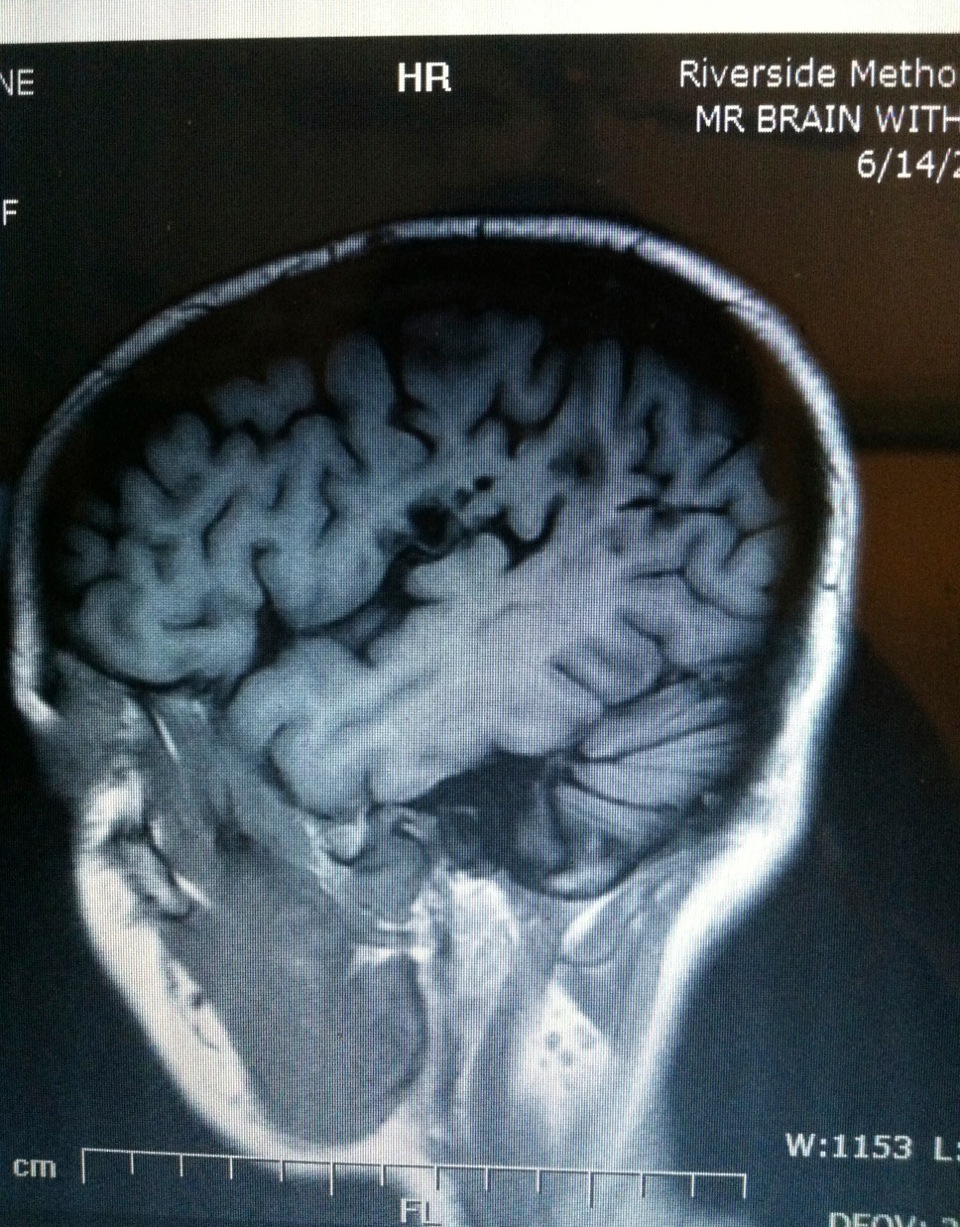

One of Kate’s brain scans